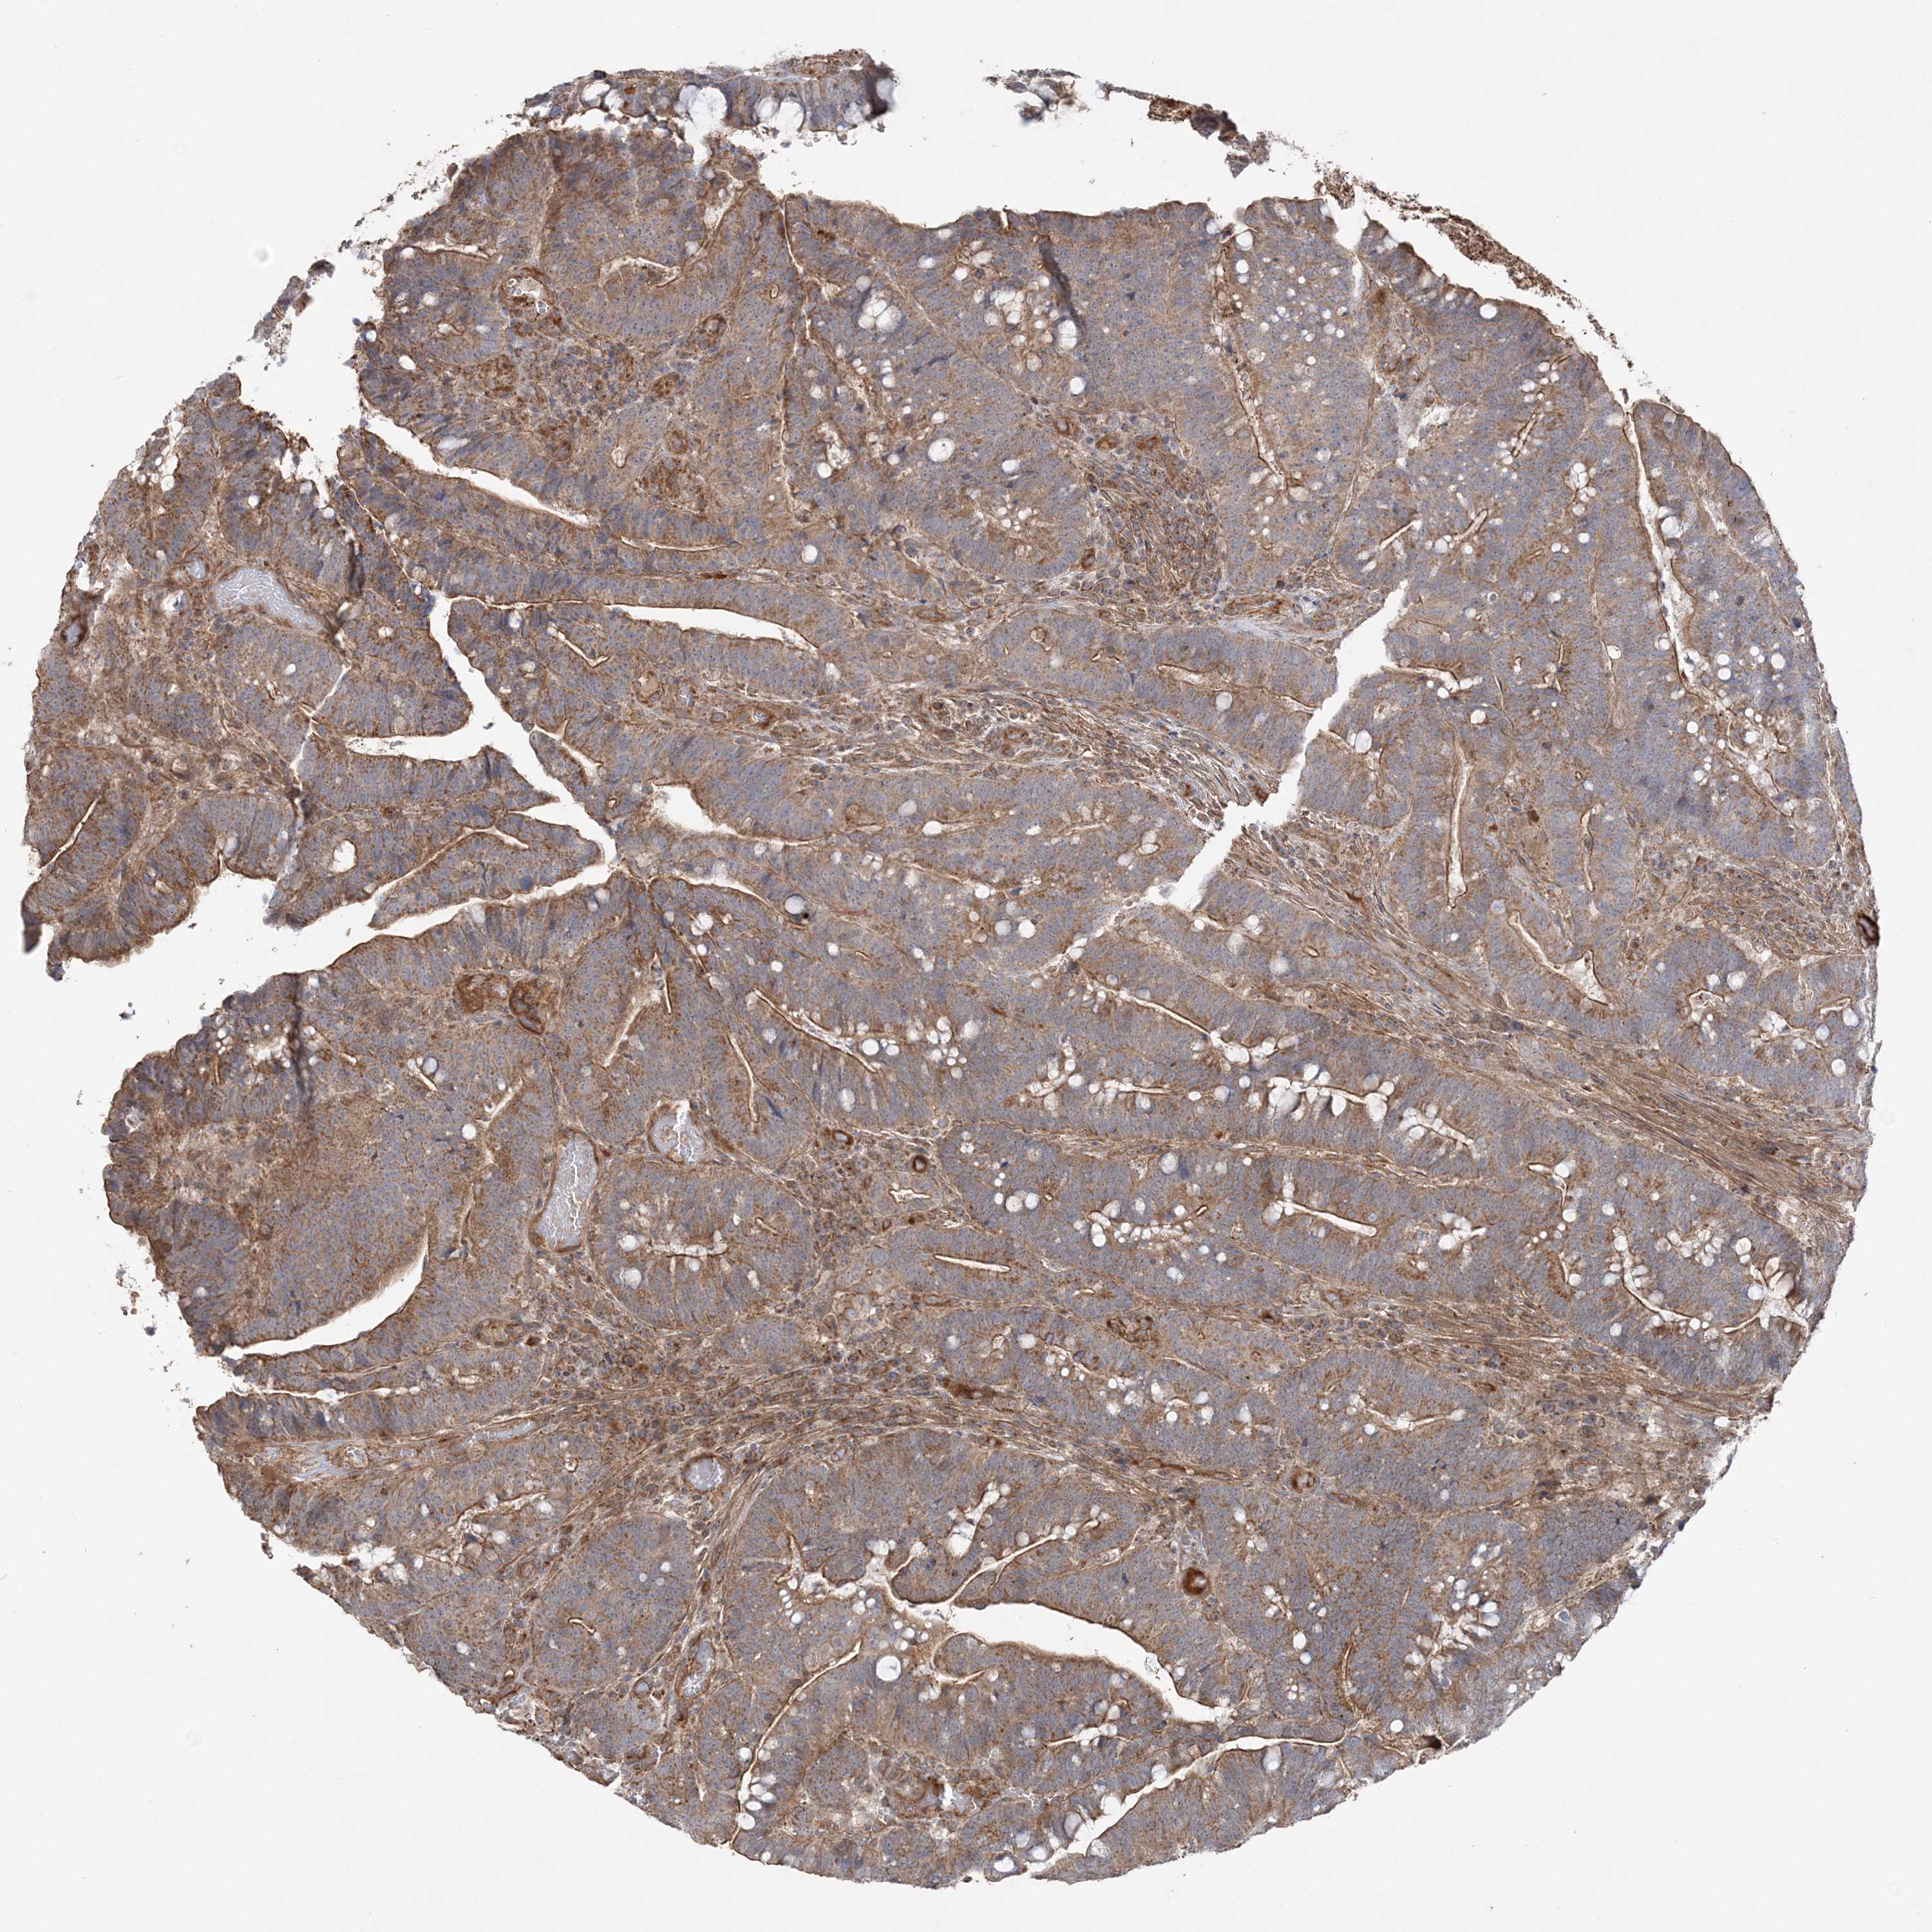

CANCER COLORECTAL CANCER Show tissue menu

Colorectal cancer

Human cancer

Colon adenocarcinoma